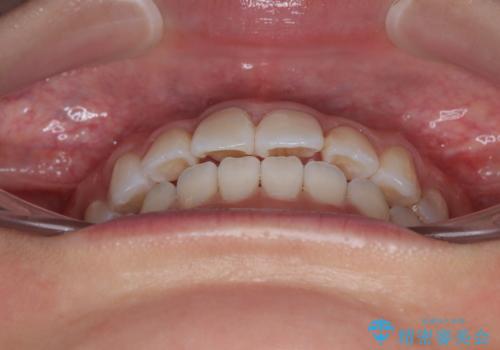

- 上下前歯のデコボコを気にして来院された患者様です。

ワイヤー矯正でもマウスピース矯正でも可能でしたが、短期間で、自身の手を煩わせることなく治療を行いたいとのことで、ワイヤー装置にて矯正治療を行うこととしました。

ご本人の中では2年近くかかるものと思っていたそうですが、1年で治療を終えることができ、大変満足していらっしゃいました。